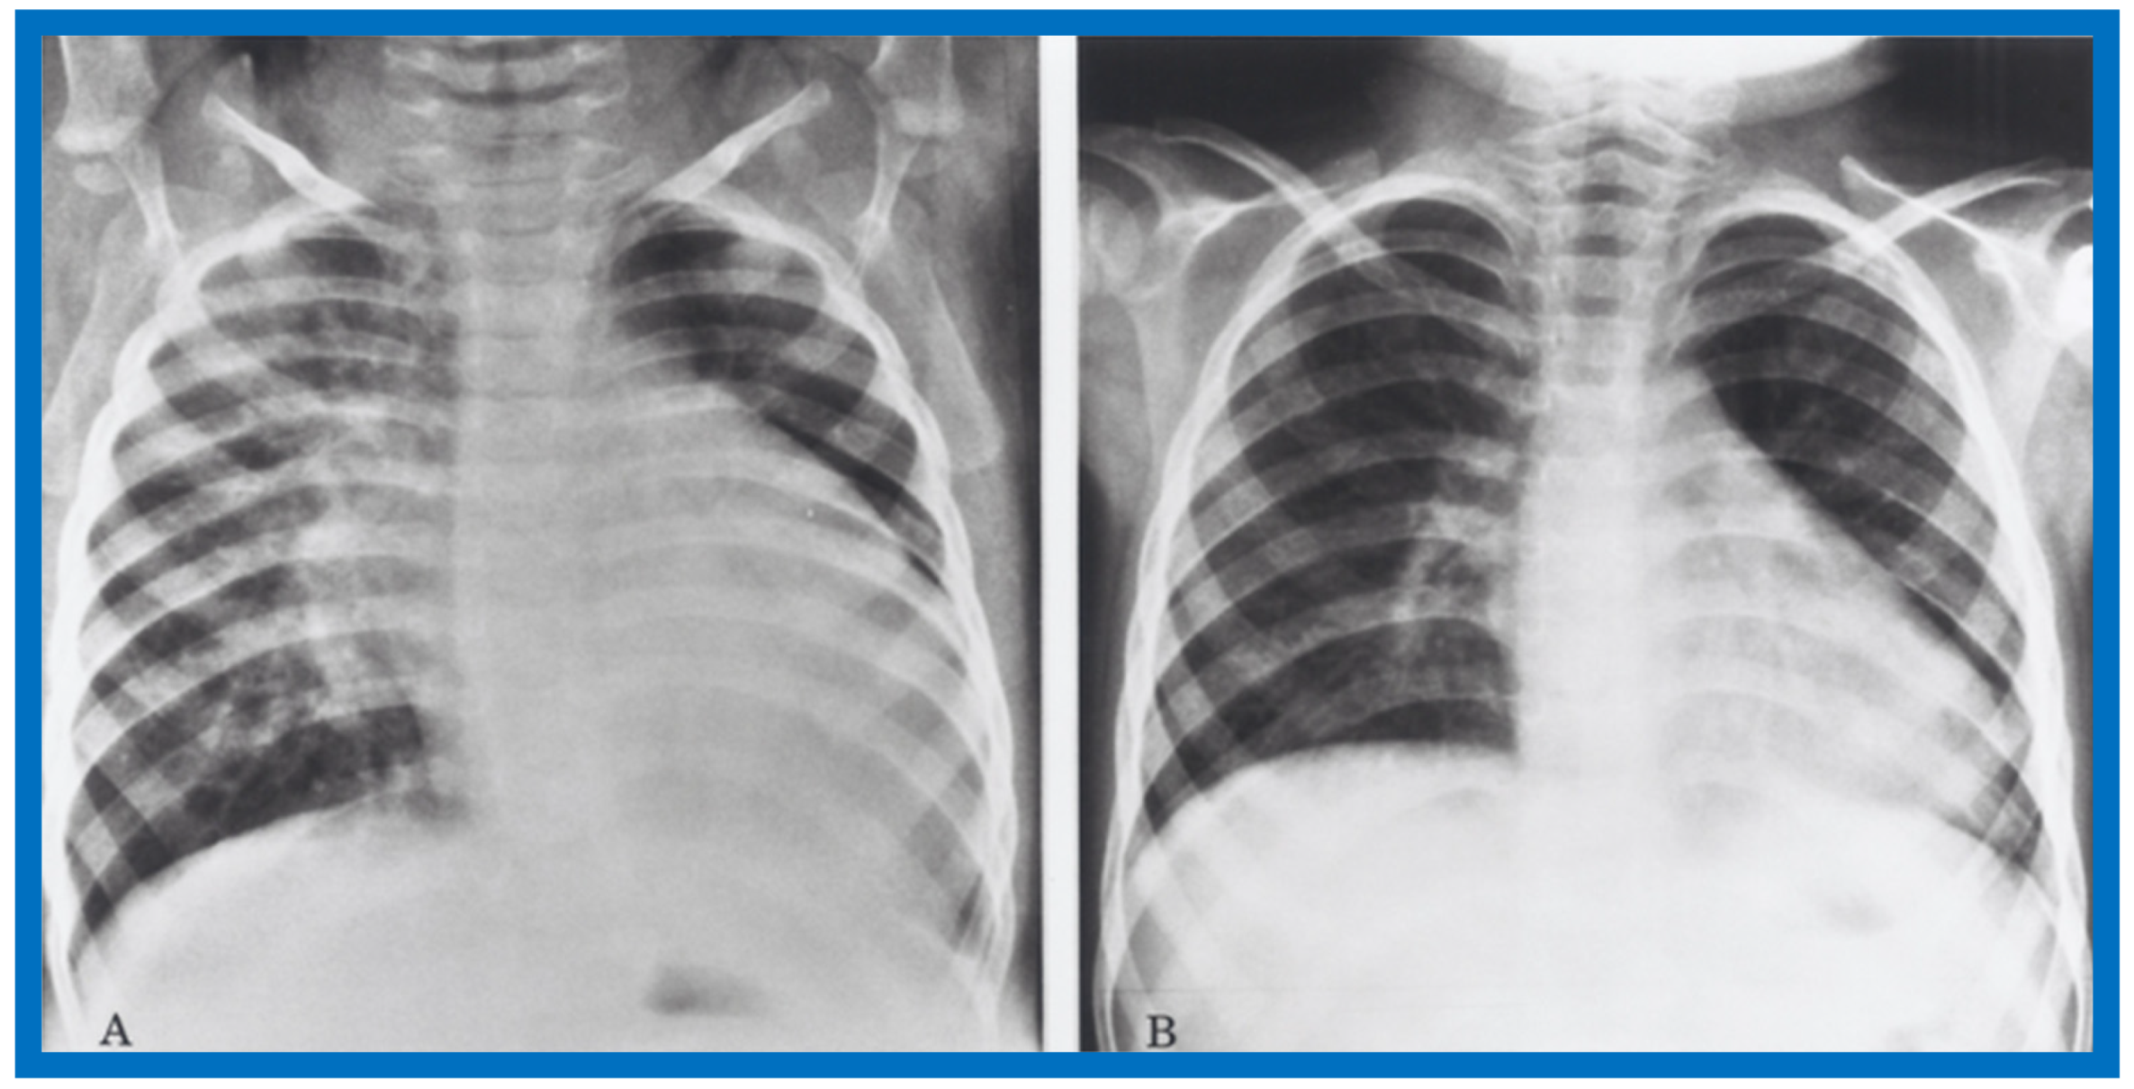

Figure 42.

Antero-posterior view of chest x-rays prior to (A) and following (B) hydralazine therapy. Moderate cardiomegaly and pulmonary venous congestion were seen prior to therapy (A) which improved remarkably after therapy (B).

Figure 43.

Antero-posterior view of chest x-rays prior to (A) and following (B) hydralazine therapy from a different infant. Moderate cardiomegaly with pulmonary venous congestion was seen prior to therapy (A) which improved remarkably after therapy (B), similar to that seen in Figure 42.